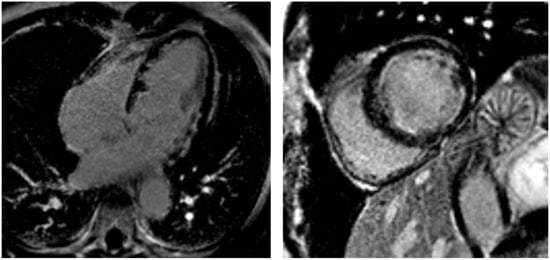

In subacute and chronic EM phases, the presence of myocardial edema is variable, while LGE typically reveals a circumferential pattern of subendocardial fibrosis [,,,], occasionally involving both ventricles (“V-shaped” aspect of the apical ventricles) [], and clearly not following a coronary distribution. This fibrotic progression, known as Loeffler cardiomyopathy (Figure 4), is particularly common in EGPA-related EM []. At this stage, it is crucial to rule out intraventricular thrombus, not always detectable by contrast echocardiography (Figure 5). Moreover, a correlation has been observed between the CMR pattern and the histopathological subtype. Notably, necrotizing EM is associated with the presence of subendocardial LGE in a greater number of LV segments, and the LGE mass is approximately double compared to forms without myocardial necrosis [].

Figure 4.

Loeffler cardiomyopathy. LGE sequences performed 5 months after the onset of eosinophilic myocarditis show a circumferential pattern of subendocardial fibrosis (hyperintense areas) in the apical four-chamber view (left) and mid-ventricular short-axis view (right). The subendocardial fibrosis does not follow a coronary distribution and produces a “V-shaped” appearance of the apical ventricles in the apical four-chamber view.